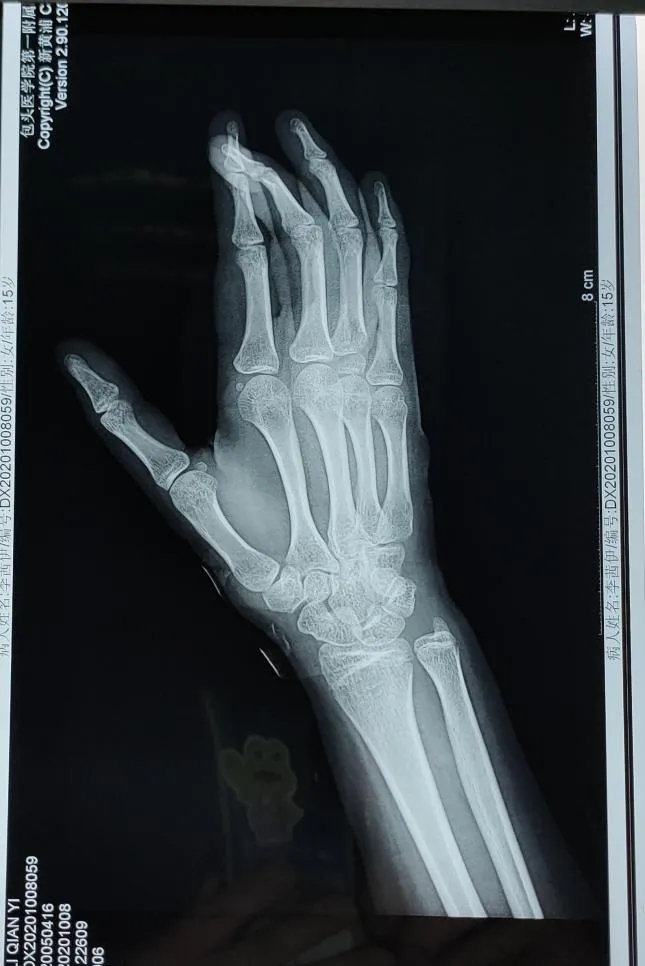

在完成相关检查后,小李被确诊为单指不全切断、开放性指骨骨折、手部指屈肌腱损伤等,手足踝外科医生连建强与同事们迅速为小李制定了手术计划,通过严谨细致的手术治疗,小李受伤的手部慢慢得到了恢复,骨折处复位良好,手指可轻微活动。目前,小李已在家属的陪伴下顺利出院,在家进行休养。